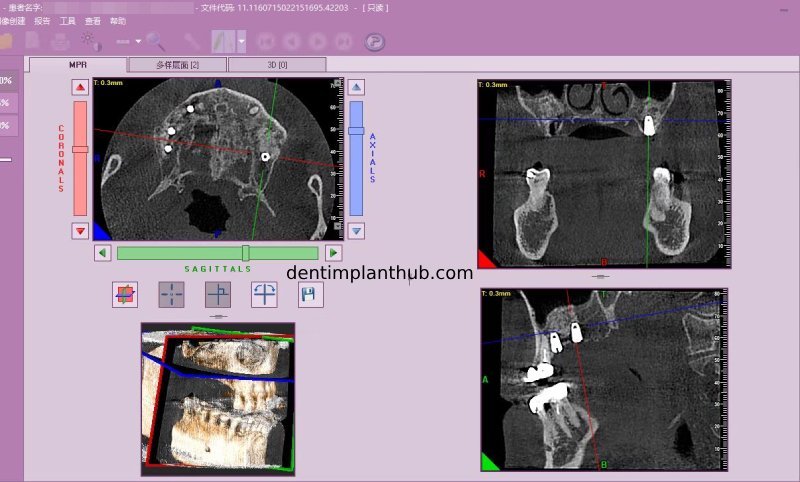

Screenshot of repeat CT on 7/1/25